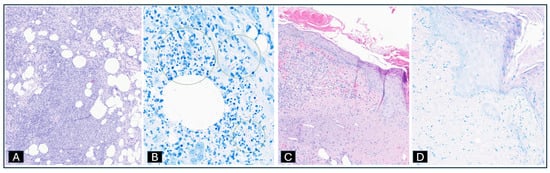

2. Case Presentation

2.1. Case 1: M. chelonae Tenosynovitis and Osteomyelitis

2.2. Case 2: Disseminated M. chelonae